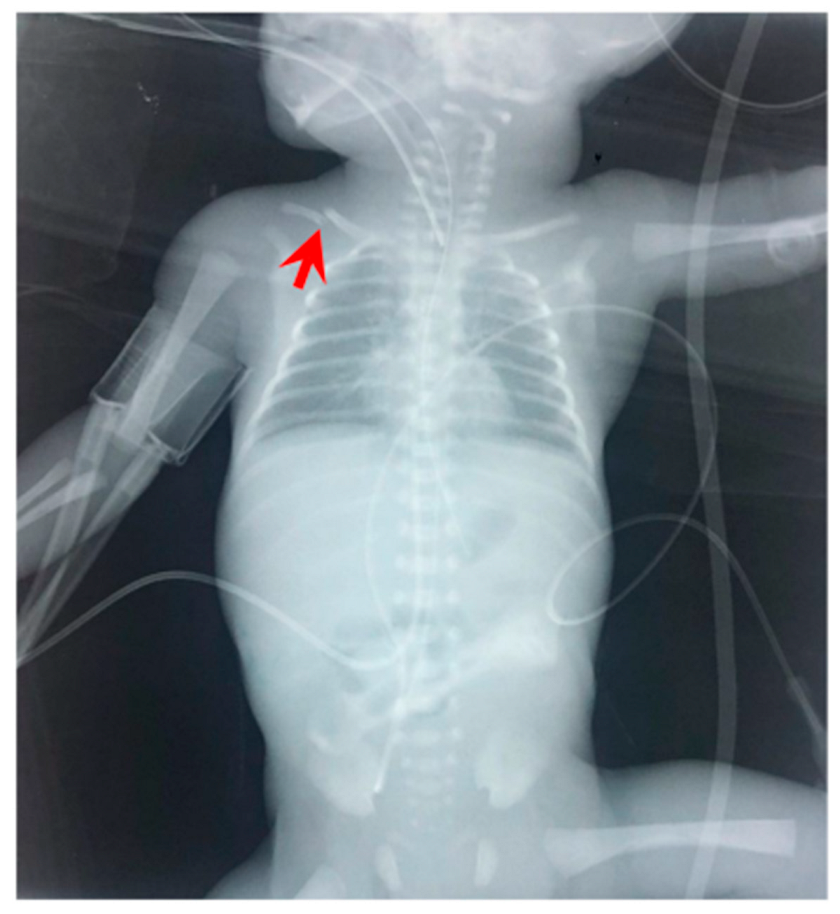

Figure 3.

Radiography of the neonate on the day of deterioration. Non-specific signal characteristics in the abdomen, such as distention and poor distribution of bowel gas. A clavicular fracture clavicle is noted on the right (red arrowhead).